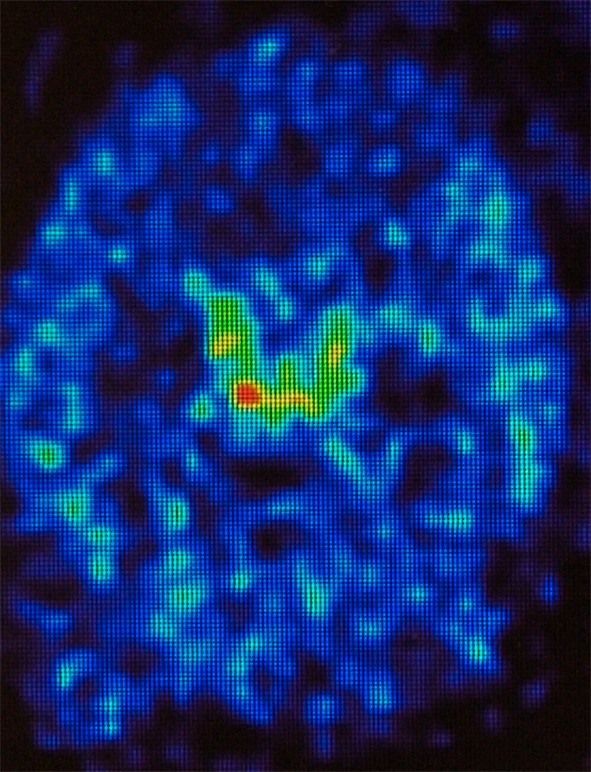

In an animal model, perispinal administration has been shown to rapidly deliver radiolabeled etanercept into the choroid plexus and cerebrospinal fluid using PET (Fig. 3) [17].

Fig. 3.

PET image showing intraventricular delivery of radiolabeled etanercept after perispinal injection. Transverse section of a living rat brain following perispinal extrathecal administration of Cu64-DOTA-etanercept, imaged 5–10 min following perispinal injection. Note enhanced signal in the choroid plexus and cerebrospinal fluid within the cerebral ventricles.

Modified from Tobinick et al. [17], used under the terms of the Creative Commons Attribution License 2.0. PET positron emission tomography